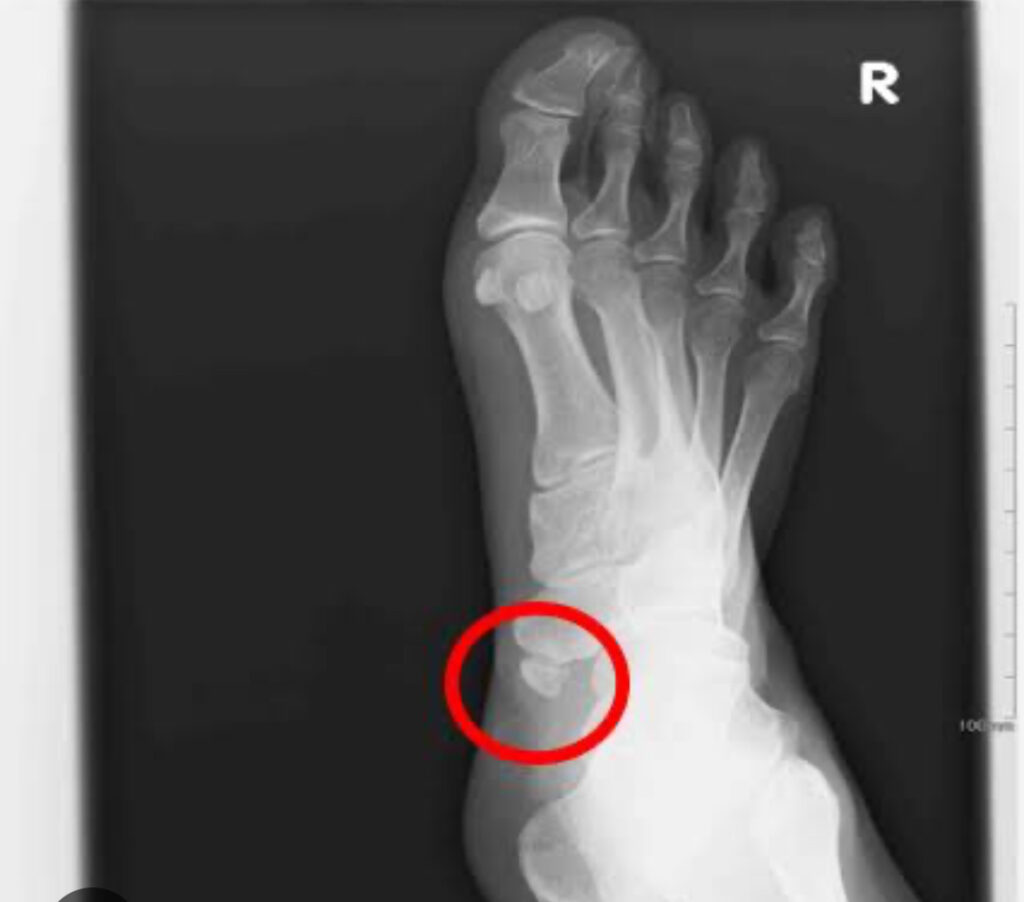

そもそも外脛骨とは?

足の土踏まず(内側アーチ)の中央部分に生じる過剰骨(普通には無い、余分にできた骨)のことを言います。外脛骨の場所は内くるぶしの下あたりに位置します。日本人の約15%の人に外脛骨があるとされています。

外脛骨があること自体は異常ではなく、通常とは形が異なっているが病気ではないもの

土踏まず(内側アーチ)の真ん中付近が痛くなるものを「有痛性外脛骨」とよびます。発症すると内くるぶし下あたりの骨の出っ張りを押さえると強く痛みます。